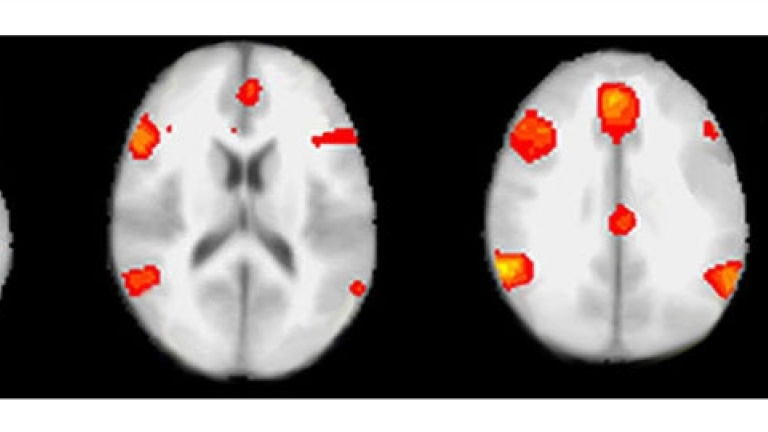

Por otra parte, las personas que mienten frecuentemente parecen acostumbrarse a ello, según otro estudio que refleja que su actividad cerebral indica que las emociones se implican cada vez menos en la decisión de seguir mintiendo.

Lo que pasa en el cerebro de los mentirosos frecuentes se ha detectado en un experimento con 80 personas que actuaban como asesores financieros de clientes desconocidos y que tenían razones para mentir, como llevarse un mayor porcentaje del dinero, pero que debían ser honrados con sus clientes. Se vio, mediante un escáner, que la actividad en ciertas áreas del cerebro -especialmente en la amígdala, muy ligada a las emociones- disminuyó en 25 de los participantes que mentían incluso si perjudicaban al cliente, algo comprensible porque no se enfrentaban a ninguna consecuencia negativa. Esta disminución llegó a ser, a medida que se repetían las pruebas, incluso predictiva de la próxima mentira.

La impunidad puede afectar a la actividad cerebral, señalan los investigadores. Su disminución, en este caso concreto, parece que influye en la decisión de mentir de nuevo, como si la persona se distanciara emocionalmente cada vez más de los efectos de sus actos.